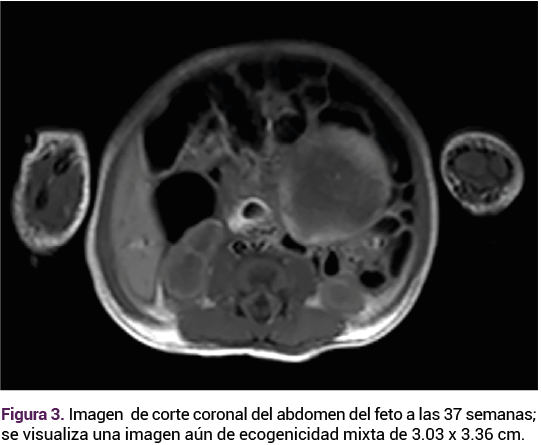

Ante las características ecográficas de la tumoración se decidió la conducta expectante, con seguimiento ecográfico. A las 37 semanas el feto continuaba con una frecuencia cardiaca de 140 lpm, peso de 3186 g, percentil 84, placenta fúndica, líquido amniótico cualitativamente normal. Sin embargo, con un aumento notable del tamaño de la tumoración intraabdominal, ahora 1 cm más grande, respecto del rastreo previo.

El embarazo finalizó mediante parto espóntaneo con un recién nacido de término, masculino, de 37 semanas por Capurro, placenta y membranas completas, con líquido amniótico de características normales, sin meconio, con talla de 50 cm, peso de 3300 g, Apgar 8-9 con permeabilidad nasal, ano y esófago, a la palpación abdominal con una tumoración de aproximadamente 7 x 5 cm fija, de consistencia dura, peristalsis normal, con el testículo izquierdo en la bolsa escrotal. A la palpación se evidenció la ausencia del testículo derecho en la bolsa escrotal. En la radiografía posteroanterior se observó la disminución del gas intestinal. Figura 3.

<strong>Figura 3</strong>

Figura 3.